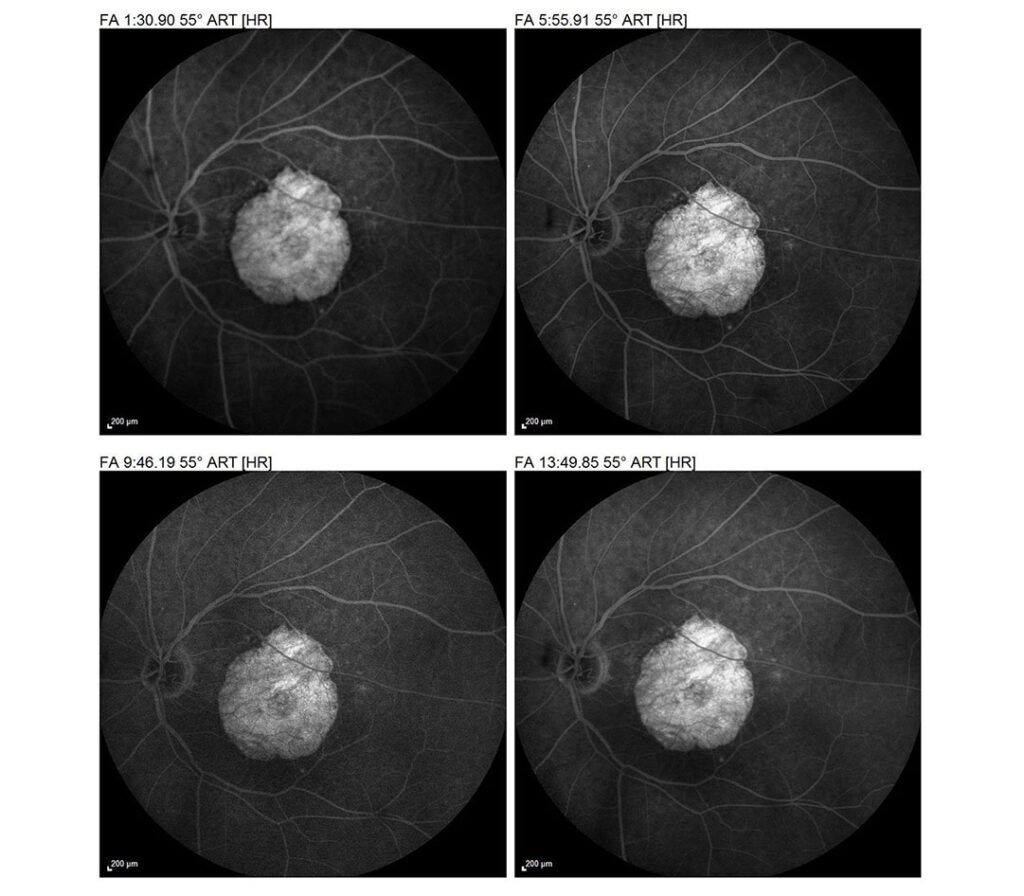

Identifiziert abnorme Blutgefässe und Undichtigkeiten.